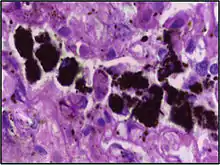

Alveolar macrophages are frequently seen to contain granules of exogenous material such as particulate carbon that they have picked up from respiratory surfaces. Such black granules may be especially common in smoker's lungs or long-term city dwellers.

| Respiratory bronchiolitis | "Smoker’s macrophages" | Yellow to light brown and finely granular[4] | Airways (especially respiratory bronchioles) | Tobacco smoking | ![]() |

Smoker's macrophage in center |